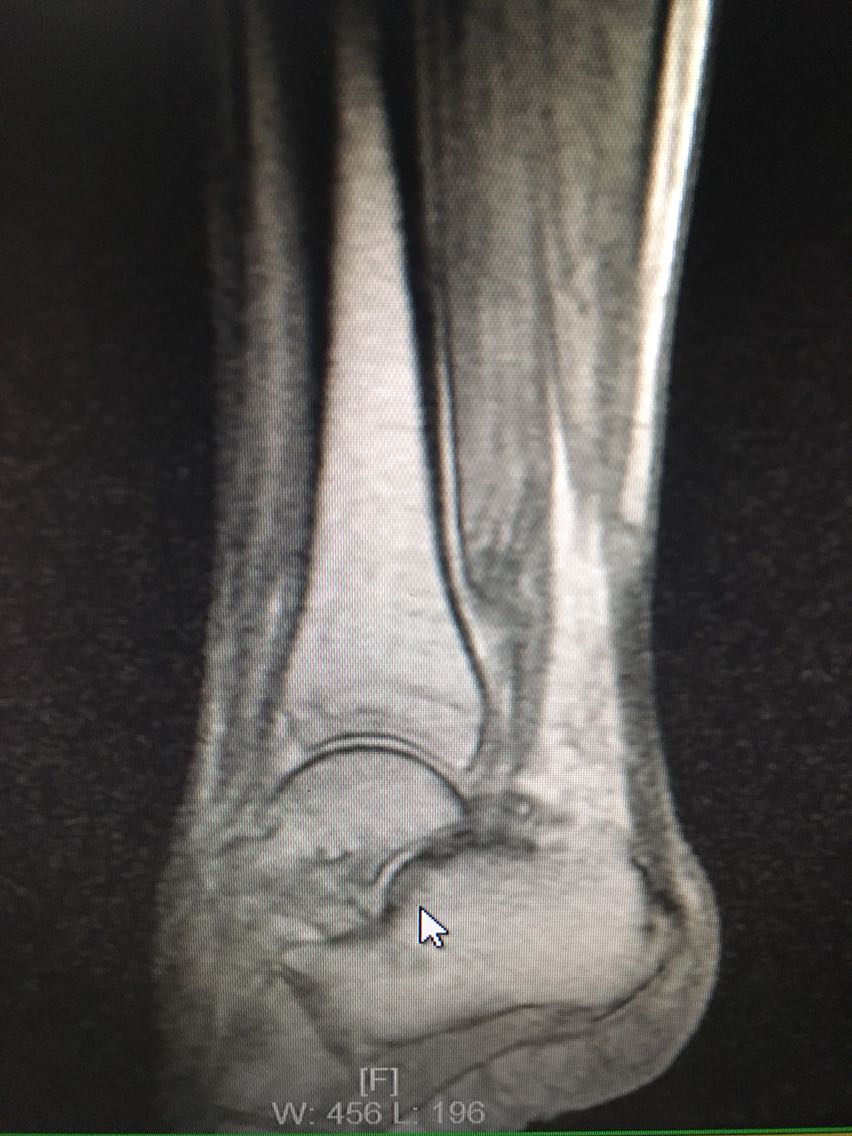

主诉:反复右侧踝关节扭伤3年余。 病史:患者F/60,自述3年前扭伤右足踝,未予以重视及治疗,后反复出现右侧踝关节扭伤,目前自觉右踝松弛,不能做剧烈运动,局部无明显疼痛。

查体:右踝关节踝前抽屉试验和内翻试验阳性,局部无压痛。 辅查:MRI检查如下

诊断:慢性踝关节不稳定 治疗:前抽屉试验阳性提示踝关节极不稳定,慢性损伤,重建是较好的选择。术中探查见距腓前韧带和跟腓韧带均极度松弛,决定取腓骨短肌腱重建;手术中以直径3.5mm挤压螺钉挤压固定,不能影响踝关节跖屈背伸角度,不能太紧。